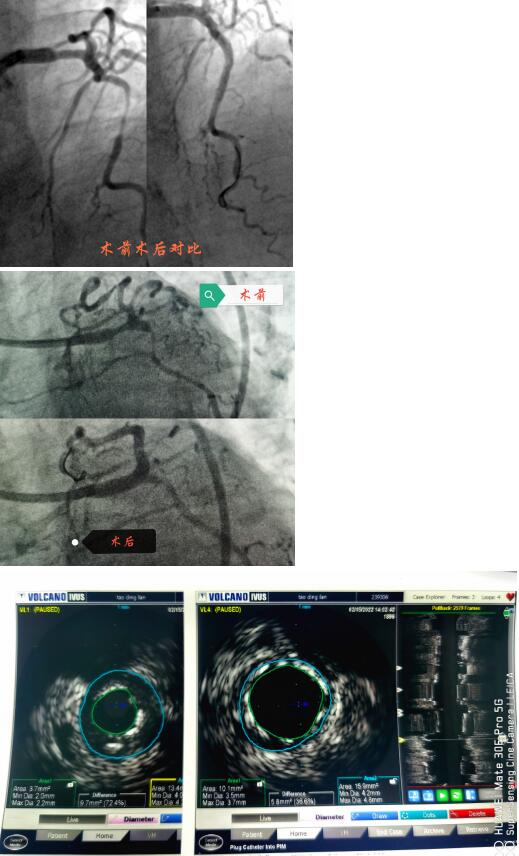

春節(jié)剛過(guò),陶奶奶的孩子們帶著陶奶奶再次來(lái)到了江寧中醫(yī)院心內(nèi)科準(zhǔn)備拆除這顆潛在的“致命炸彈”。韋鋒主任反復(fù)研究陶奶奶的前期手術(shù)影像,心中擬定著多個(gè)手術(shù)方案。經(jīng)過(guò)充分準(zhǔn)備,2月15日,韋鋒主任再次為陶奶奶進(jìn)行了介入手術(shù)。術(shù)中通過(guò)血管內(nèi)超聲(IVUS)精細(xì)、準(zhǔn)確評(píng)估陶奶奶的冠脈病變情況,發(fā)現(xiàn)陶奶奶的左主干最小管腔面積僅僅3.7mm2,;前降支近段全程鈣化,最嚴(yán)重處呈270度的環(huán)形鈣化,最小管腔面積僅僅2.1mm2;回旋支開(kāi)口正常,回旋支近端最小管腔面積1.8mm2。韋鋒主任根據(jù)IVUS的結(jié)果,改變了原來(lái)擬定的DKCRUSH術(shù)式,決定采用藥物球囊和藥物涂層支架相結(jié)合的方式處理病變(LCX藥物球囊,LM-LAD植入支架),經(jīng)過(guò)近2個(gè)小時(shí)的手術(shù),陶奶奶的冠脈血管又“完美”地回來(lái)了。

韋鋒主任術(shù)中在仔細(xì)研究陶奶奶的IVUS結(jié)果,指導(dǎo)手術(shù)更精確的進(jìn)行。